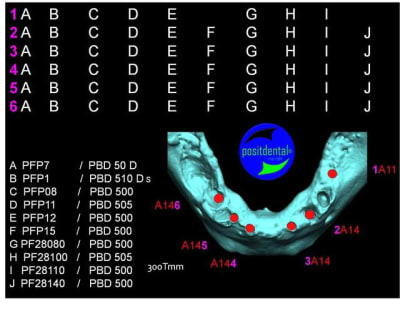

en attendant la pano voici les coupes de la S.I.A.O.

Image33_nwzawb.jpg

Image34_ixvkww.jpg

Image35_orinjf.jpg

Image39_nacsid.jpg

Image40_hkzycw.jpg

Image41_egzryy.jpg

Image42_p57obk.jpg

Image43_jgylho.jpg

Image44_ysqyf8.jpg

Image45_d112br.jpg

Image46_u9eg6l.jpg

Image47_yffnwq.jpg

Image48_ptc9lw.jpg

Image30_exkkml.jpg

Image31_p13zyn.jpg

Image32_ffzd3q.jpg

Image36_jfzwrz.jpg

Image37_inavxh.jpg

Image38_jfa54w.jpg

bien...mais dans certaines zones,surtout postérieures, j'aurais mis plus gros...surtout qu'il y a la place...